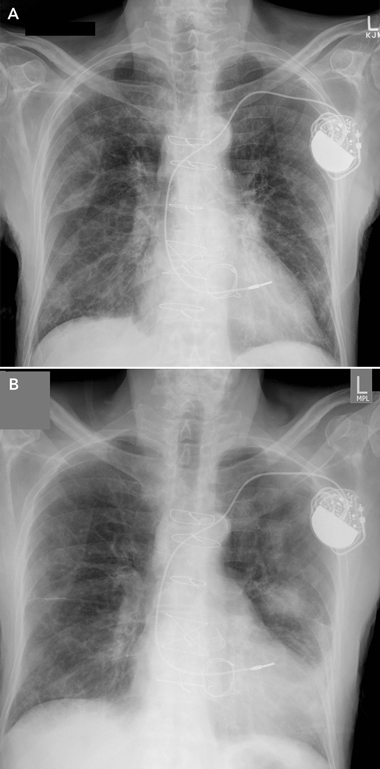

Chest x-ray at presentation showed air bronchograms at the right lower zone (Box 2). Our patient was admitted and treated for right lower lobe pneumonia with intravenous antibiotics. He was also prescribed high-dose oral steroids, with gradual tapering of doses. A computed tomography scan showed probable right lower chest infection.

During the early weeks of his hospitalisation, the patient had further episodes of acute dyspnoea, and repeat chest x-rays showed bilateral migratory opacities (Box 3). Acute episodes of dyspnoea were treated with high-dose oral steroids and intravenous antibiotics; a regular regimen of low-dose steroids was maintained between episodes. During each acute episode, his biochemistry results showed an inflammatory response, with varying elevated serum levels of C-reactive protein (CRP): 243 mg/L; 332 mg/L; 73 mg/L; 16 mg/L; 148 mg/L; and 90 mg/L (reference range [RR], < 5.0 mg/L). With treatment, the CRP level fell to 5.3 mg/L. Repeated blood and urine cultures produced no growth.